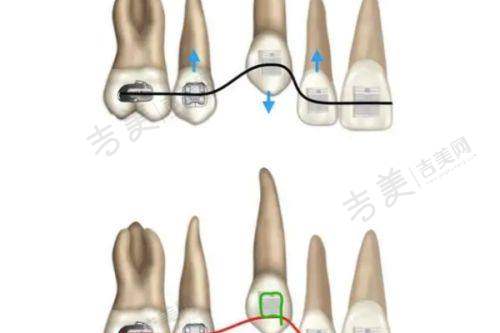

烟台莱山德韩口腔门诊部成立于2022年6月20日,公司规模为100 - 499人。门诊部设有多个专精科室,涵盖了口腔种植、口腔正畸、口腔修复、口腔综合治疗等多个领域。其中,数字化种植中 心和美颜正畸中 心是其特色科室。数字化种植中 心配备了德国卡瓦口腔CT、3D导板打印系统等精良设备,实现了“数字化种植”,能够为患者提供精细、效率高的种植方案。美颜正畸中 心引入了美国隐适美iTero口扫仪,5分钟即可生成牙齿3D模型,并动态演示矫正全过程,为患者提供个性化的正畸方案。此外,门诊部还注重服务质量和患者体验,为患者提供全方面的口腔医疗服务。

烟台莱山德韩口腔门诊部拥有多个特色项目,具有显著的独特之处和优势。在数字化种植中 心,配备德国卡瓦口腔CT、3D导板打印系统,实现“数字化种植”。ALL - ON - 4半口种植仅需4颗植体半口牙,支持即刻负重,术后24小时戴临时冠;百康特种植套餐1280元起(含植体 + 基台 + 牙冠),瑞士诺贝尔高端植体可选,能有效避开神经,全程几乎微痛。美颜正畸中 心引入美国隐适美iTero口扫仪,5分钟生成牙齿3D模型,并动态演示矫正全过程。金属自锁托槽矫正周期缩短30%,儿童配合度更高;隐形矫正双膜技术(时代天使/隐适美),薄厚膜交替佩戴加速牙齿移动;价格透明,金属托槽4980元起,全隐形矫正8888元起(2025年活动价)。此外,门诊部还设有独立诊室,搭配空气系统,保护隐私的同时降低交叉感染风险;器械消毒采用“六步灭菌法”,实现“一人一机一用”。